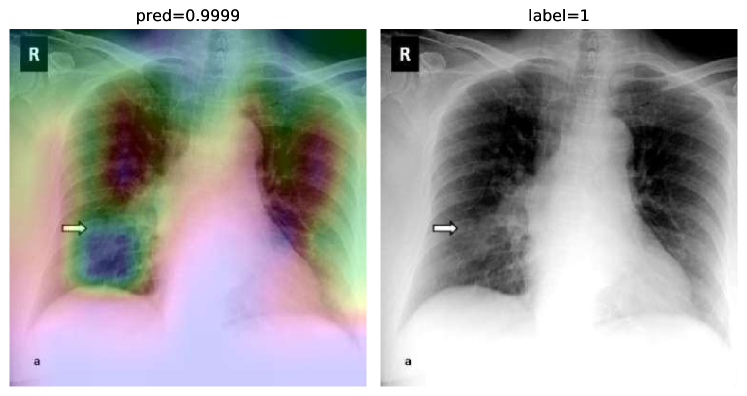

While text removal methods can prevent overfitting, we can simply force the model to look into the lungs in order to address both problems in one effort. To accomplish this task, a U-Net based segmentation illustrated in Fig. 4 is applied to the input images before enhancements. Visualization results for COVID-CXNet with the ROI-segmentation block are shown in Fig. 18.

Figure 18: Grad-CAM visualization of the proposed model, trained with lung-segmented CXRs, over sample cases.

A figure with more Grad-CAMs is attached in Appendix B. From Fig. 18, it can be observed that COVID-CXNet with ROI-segmentation has delivered superior performance regarding the localization of pneumonia features. Worthwhile to mention that image augmentation is expanded by adding zoom-in, zoom-out, and brightness adjustment. Label smoothing is also applied to the loss function.

The proposed method has shown a negligible drop in metric scores; accuracy is decreased by 0.42%, and f-score is declined by 0.02. This decrease is a result of training with a larger dataset and accurately segmented ROIs, which means it has become more robust against unseen samples. There is a trade-off between catching good features and higher metric scores; while better features result in a more generalized model, high metric scores may indicate overfitting.